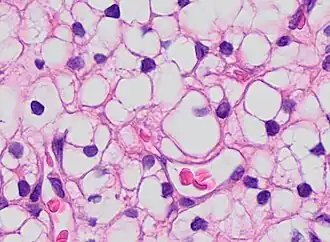

The most commonly used stain in histology is a combination of hematoxylin and eosin (often abbreviated H&E). Hematoxylin is used to stain nuclei blue, while eosin stains the cytoplasm and the extracellular connective tissue matrix of most cells pink. There are hundreds of various other techniques which have been used to selectively stain cells. Other compounds used to color tissue sections include safranin, Oil Red O, congo red, silver salts and artificial dyes. Histochemistry refers to the science of using chemical reactions between laboratory chemicals and components within tissue. A commonly performed histochemical technique is the Perls' Prussian blue reaction, used to demonstrate iron deposits in diseases like Hemochromatosis.[2]